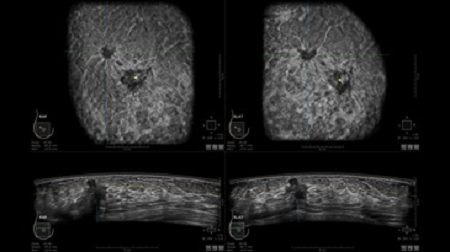

GE INVENIA ABUS – это современный УЗИ аппарат, который создан для точной и эффективной диагностики сканирования с высокой плотностью молочных желез. Выявляемость патологий раковых и предраковых стадий заболевания составляет 55%, что в конечном счете позволяет ставить врачу точные и своевременные диагнозы. Традиционные методы использования маммографии не показывают такой выявляемости, ограничиваясь лишь 3-38%.

УЗИ-аппарат GE INVENIA ABUS позволяет проводить максимально операторонезависимые процедуры, что значительно снижает риск неправильной постановки диагноза и сопутствующие издержки на обработку информации. Система готовит отчет в течение 3-х минут после сканирования, это безусловное преимущество по сравнению с обычным УЗИ сканером.

• датчик с изогнутой апертурой для качественного исследования

• сканирование одной грудной железы в трех проекциях не более 60 сек.;

• обработка результатов за три минуты.

• Отображение объемных 3D ультразвуковых изображений, которые состоят из традиционных поперечных и воссозданных коронарных и сагиттальных проекций

• Стандартизованная ориентация изображения: «толстый срез» в коронарной плоскости; поперечная; сагиттальная плоскость; радиальный и антирадиальный поворот изображения; просмотр исключительно области интереса